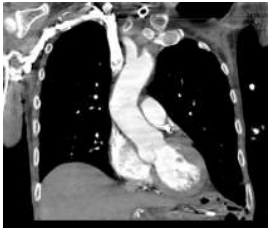

A imagem exibe uma reconstrução de um exame de imagem do tórax, observe:

Considerando a técnica utilizada e a densidade das estruturas ósseas, assinale a alternativa que define CORRETAMENTE o tipo de exame realizado: